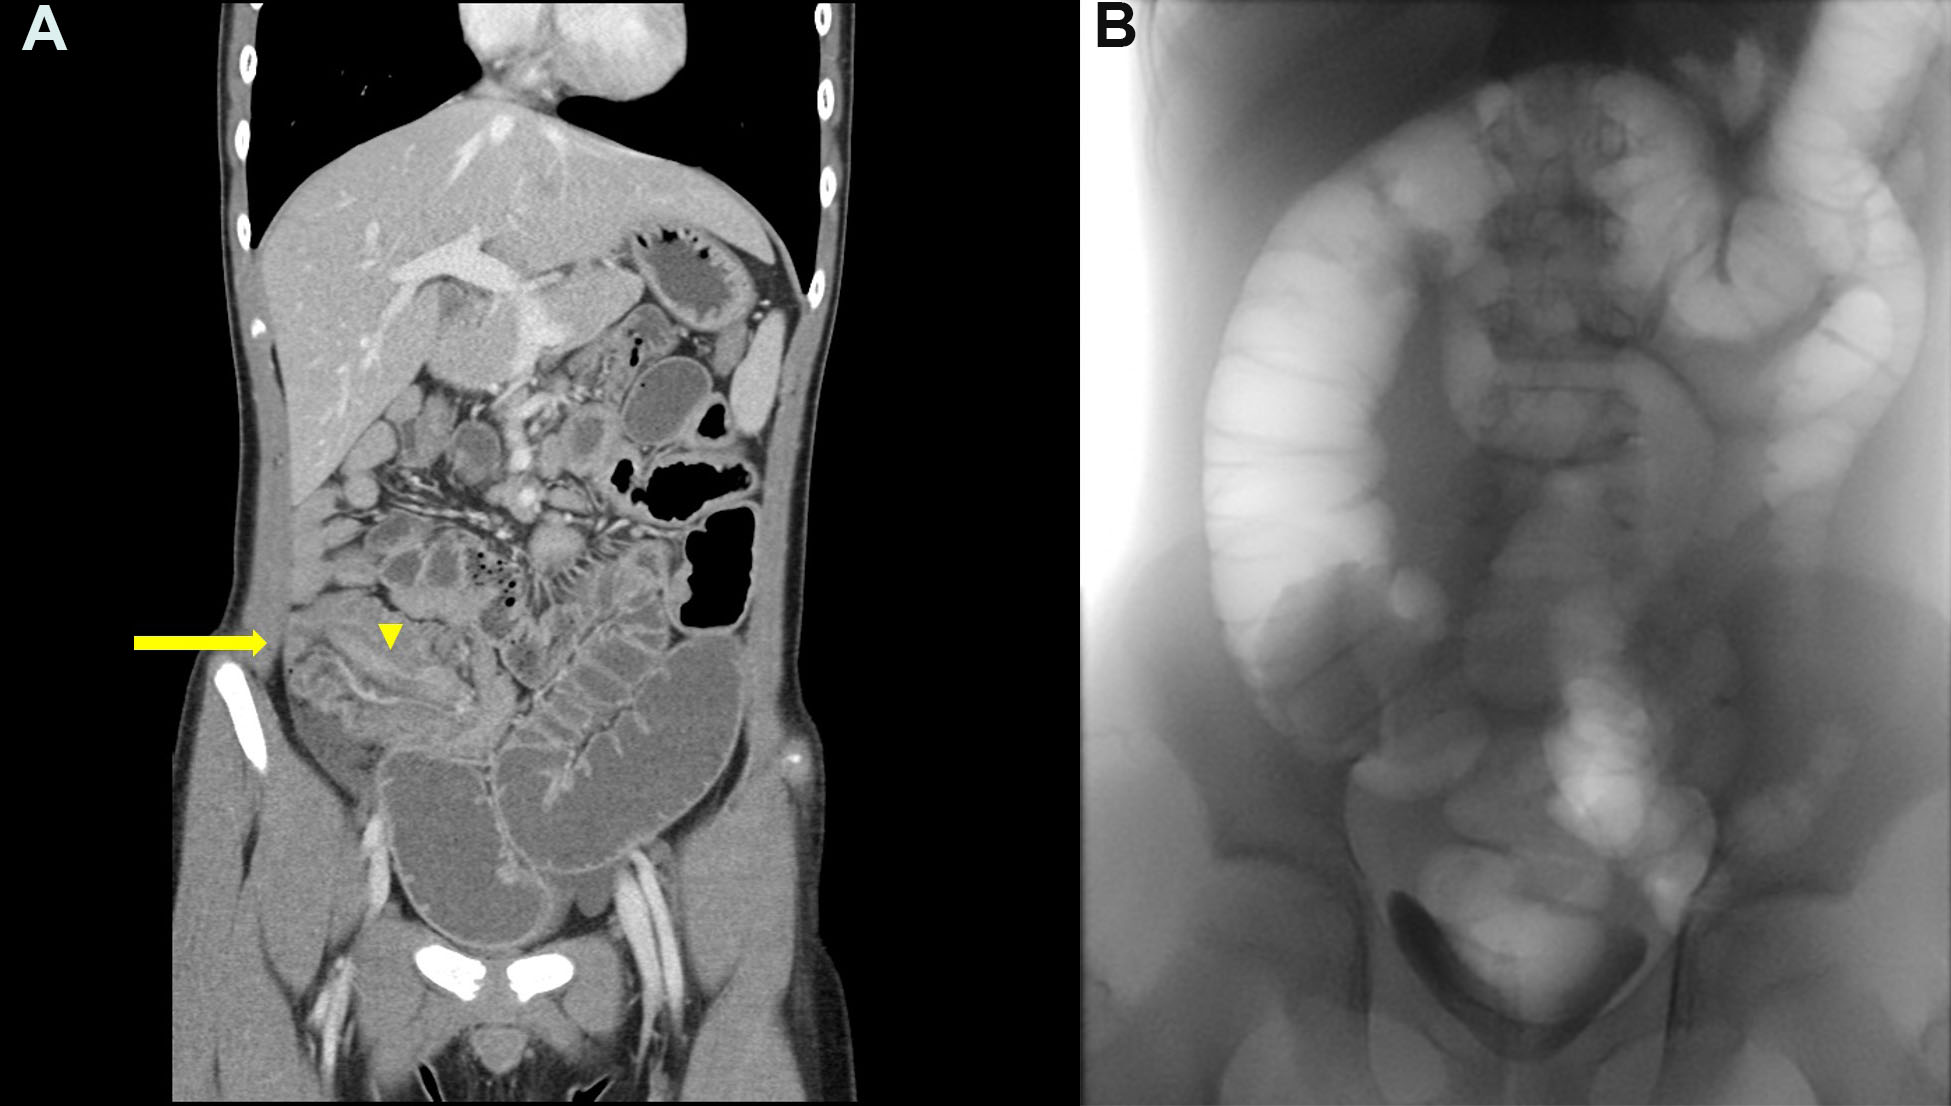

Case 2: A CT scan revealed ileocolic intussusception with abnormal mural thickening of the terminal ileum (Figure 3A). The lesion did not improve after three pneumatic reductions (Figure 3B). During the colonoscopy, we noted the intussuscipiens in the ascending colon (Figure 4).

Figure 3

Figure 3. Initial imaging studies of Case 2. A. An abdominal CT scan demonstrated an obstructive ileus with an ileocolic intussusception (indicated by the arrow) and an asymmetrically enhanced bowel wall thickening (indicated by the arrowhead). B. Fluoroscopy revealed incomplete reduction after three attempts at a pneumatic reduction.